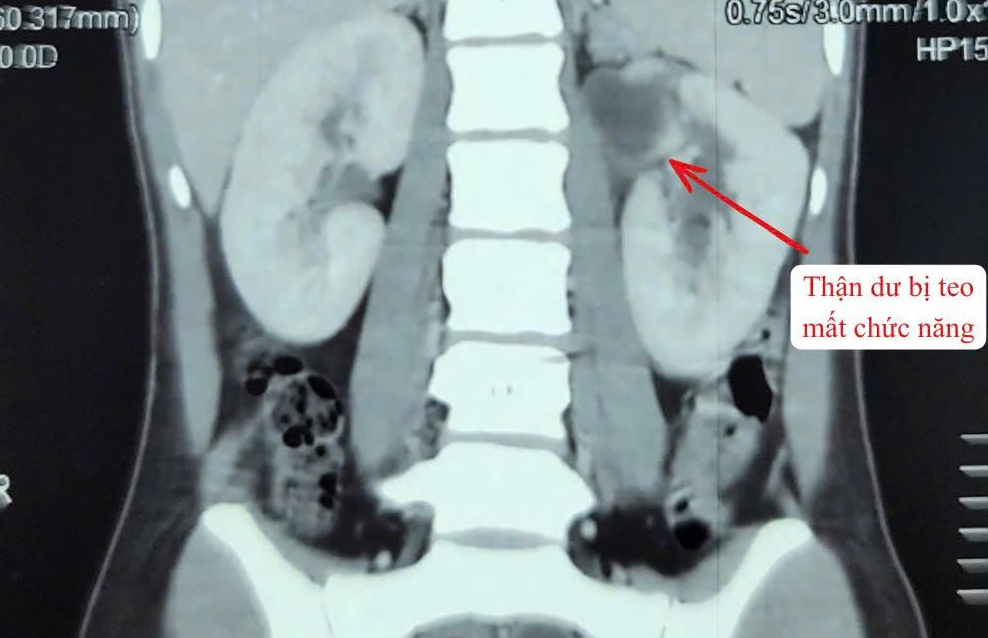

Người bệnh nhập viện trong tình trạng sốt cao, đau vùng hông trái. Qua thăm khám lâm sàng và thực hiện các xét nghiệm cận lâm sàng, các bác sĩ chẩn đoán bệnh nhân mắc dị tật thận - niệu quản đôi bên trái (tổng 3 thận). Trong đó, một thận đã mất chức năng, niệu quản giãn lớn bất thường, chứa nhiều mủ gây nhiễm trùng nặng.

Sau khi hội chẩn chuyên môn và kiểm soát tình trạng viêm nhiễm, ê-kíp Khoa Ngoại thận tiết niệu đã quyết định phẫu thuật cắt bỏ toàn bộ hệ thống thận và niệu quản bên trái đã mất chức năng nhằm loại bỏ ổ nhiễm trùng và phòng ngừa biến chứng.